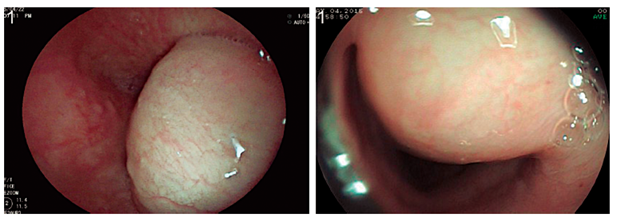

Se presenta el caso clínico de una paciente de 56 años sin antecedentes médicos de importancia, quien desarrolló disfagia para sólidos de 2 meses de evolución, con pérdida de 4 kg de peso durante ese lapso, por lo que se indicó una endoscopia digestiva superior. Se encontró una lesión de 30 mm hacia el tercio inferior del esófago en la pared anterior derecha, de apariencia subepitelial, cubierta por una mucosa sin alteraciones (Figura 1).

Ante el hallazgo, se decidió realizar la EUS radial esofágica en la que se encontró una lesión dependiente de la tercera capa esofágica, pero de características hipoecoicas más que anecoicas, por lo que se realizó una EUS-FNA con estudio citológico rápido. Se encontró abundante material mucoso que evidenció la presencia de células epiteliales y contenido de mucina, sin evidencia de cambios citopatológicos malignos (Figura 2).